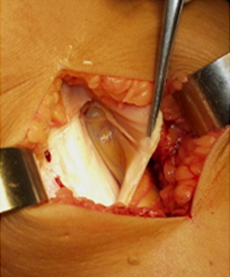

Incisione cutanea mediale sulla tibia prossimale

Si effettua il taglio della tibia e si apre la sede osteotomica dei gradi esatti precedentemente calcolati sulla radiografia